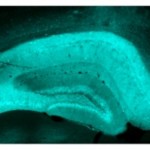

Por lo tanto, cómo funciona un antidepresivo en la bioquímica y el comportamiento en un ratón en el que la proteína CREB se elimina sólo en el hipocampo en comparación con un ratón de tipo salvaje en el que se sobreexpresa CREM dejar que los investigadores desentrañar la influencia relativa de CREB y CREM en la farmacología de un antidepresivo . Ellos vieron los mismos resultados en cada tipo de línea de ratón – aumento de la generación de las células nerviosas en el hipocampo y una respuesta más rápida a los antidepresivos . Sus hallazgos aparecen en la revista Journal of Neuroscience.

El tiempo acelerado a acercarse el tratamiento en ratones con el medicamento fue acompañado por un aumento en el nuevo crecimiento del nervio en el hipocampo.